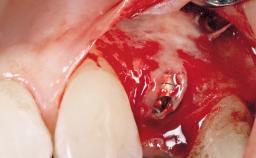

Late Flapless Placement of an Implant in a Maxillary Left Central Incisor Site

A 39-year-old male patient presented with a chief complaint of discomfort and gingival discoloration around his maxillary left central incisor. He was in good general health and was a non-smoker. His past dental history was significant because of the traumatic fracture of tooth 21 in a sporting accident at age 13. Initial dental treatment included endodontic therapy and a full-coverage restoration. The patient became symptomatic 5 years later, when structural failure of the tooth resulted in the dislodgment of the crown. Endodontic retreatment, apical surgery, and post-and-core restoration were performed.

| Bone Augmentation | Horizontal|Staged |

| Augmentation Materials | Xenogenous|Membrane |